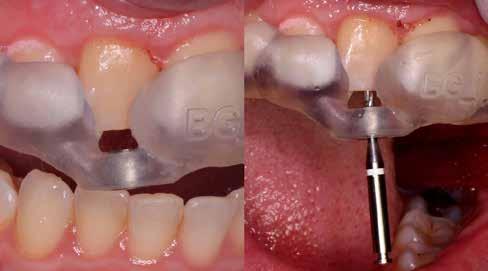

1. a–f ábrák: A cingulumon keresztül gömbfúróval kialakított hozzáférés a trepanációs kavitás labiális irányba történő túlzott mértékű kiterjesztését eredményezheti, és ez lényegesen növelheti a perforáció esélyét (a). A guttapercha átsejlik a lágyrészek alatt (b). Klinikailag igazolt perforáció (c). A preoperatív sagittális irányú CBCT-szeleten jól látható a labiális perforáció (d). Labiális irányú perforáció (fekete nyíl; e). A tényleges gyökércsatorna (piros nyíl; f).

A frontfogakban történő hozzáférési nyílás kialakítása

A frontfogakban a hozzáférési nyílás kialakítását hagyományosan a fogak linguális vagy palatinális felszínén, a cingulumon keresztül egy gömbfúró segítségével kezdjük. A linguálisan elhelyezkedő kiemelkedés teljes eltávolítása, továbbá a pulpaszarvak teljes feltárása egy háromszög alakú hozzáférési nyílást eredményez. 7 Ezt a módszert a fogak esztétikai megjelenésének megőrzése érdekében fejlesztették ki. Ez azonban időnként a saját foganyag indokolatlan eltávolításával, a trepanációs kavitás labiális irányba történő túlzott kiterjesztésével, perforációval, valamint a fog kritikus helyen, a pericervikális dentin (PCD) területén történő meggyengítésével jár (1. a–f és 2. a-b ábrák). 19 Felmerült, hogy a pericervikális dentin rendkívül fontos szerepet játszik a rágóerő gyökerek irányába történő továbbításában, és elképzelhető, hogy a gyökérkezelt fogak hosszú távú megtartása szempontjából a legfontosabb tényező az ép pericervikális dentin megőrzése lehet. 20 A cingulumon keresztül történő hozzáférési nyílás

5. a–l. ábrák: Az incisális élen keresztül kialakított hozzáférés lehetővé teszi a pericervikális dentin megőrzését. Kalcifikáció esetén CBCT-felvétel készítése hasznosnak bizonyulhat a hozzáférési nyílás tervezése során (a–d) . Minden fog koronai helyreállítása a gyökértömés elkészítésével egyidejűleg történt. A négyéves (e–h) és a kétéves (i–l) kontrollok alkalmával készített röntgenfelvételeken teljes gyógyulás látható. Mindkét fog tünetmentes és funkcióképes volt. (Dr. Viraj Vora esetei)

kialakítása során fennáll a fog labiális irányú perforációjának veszélye, mivel ilyenkor a foganyag elvételét labiális irányú fúrótartással kezdjük. Nemrégiben újragondolták a